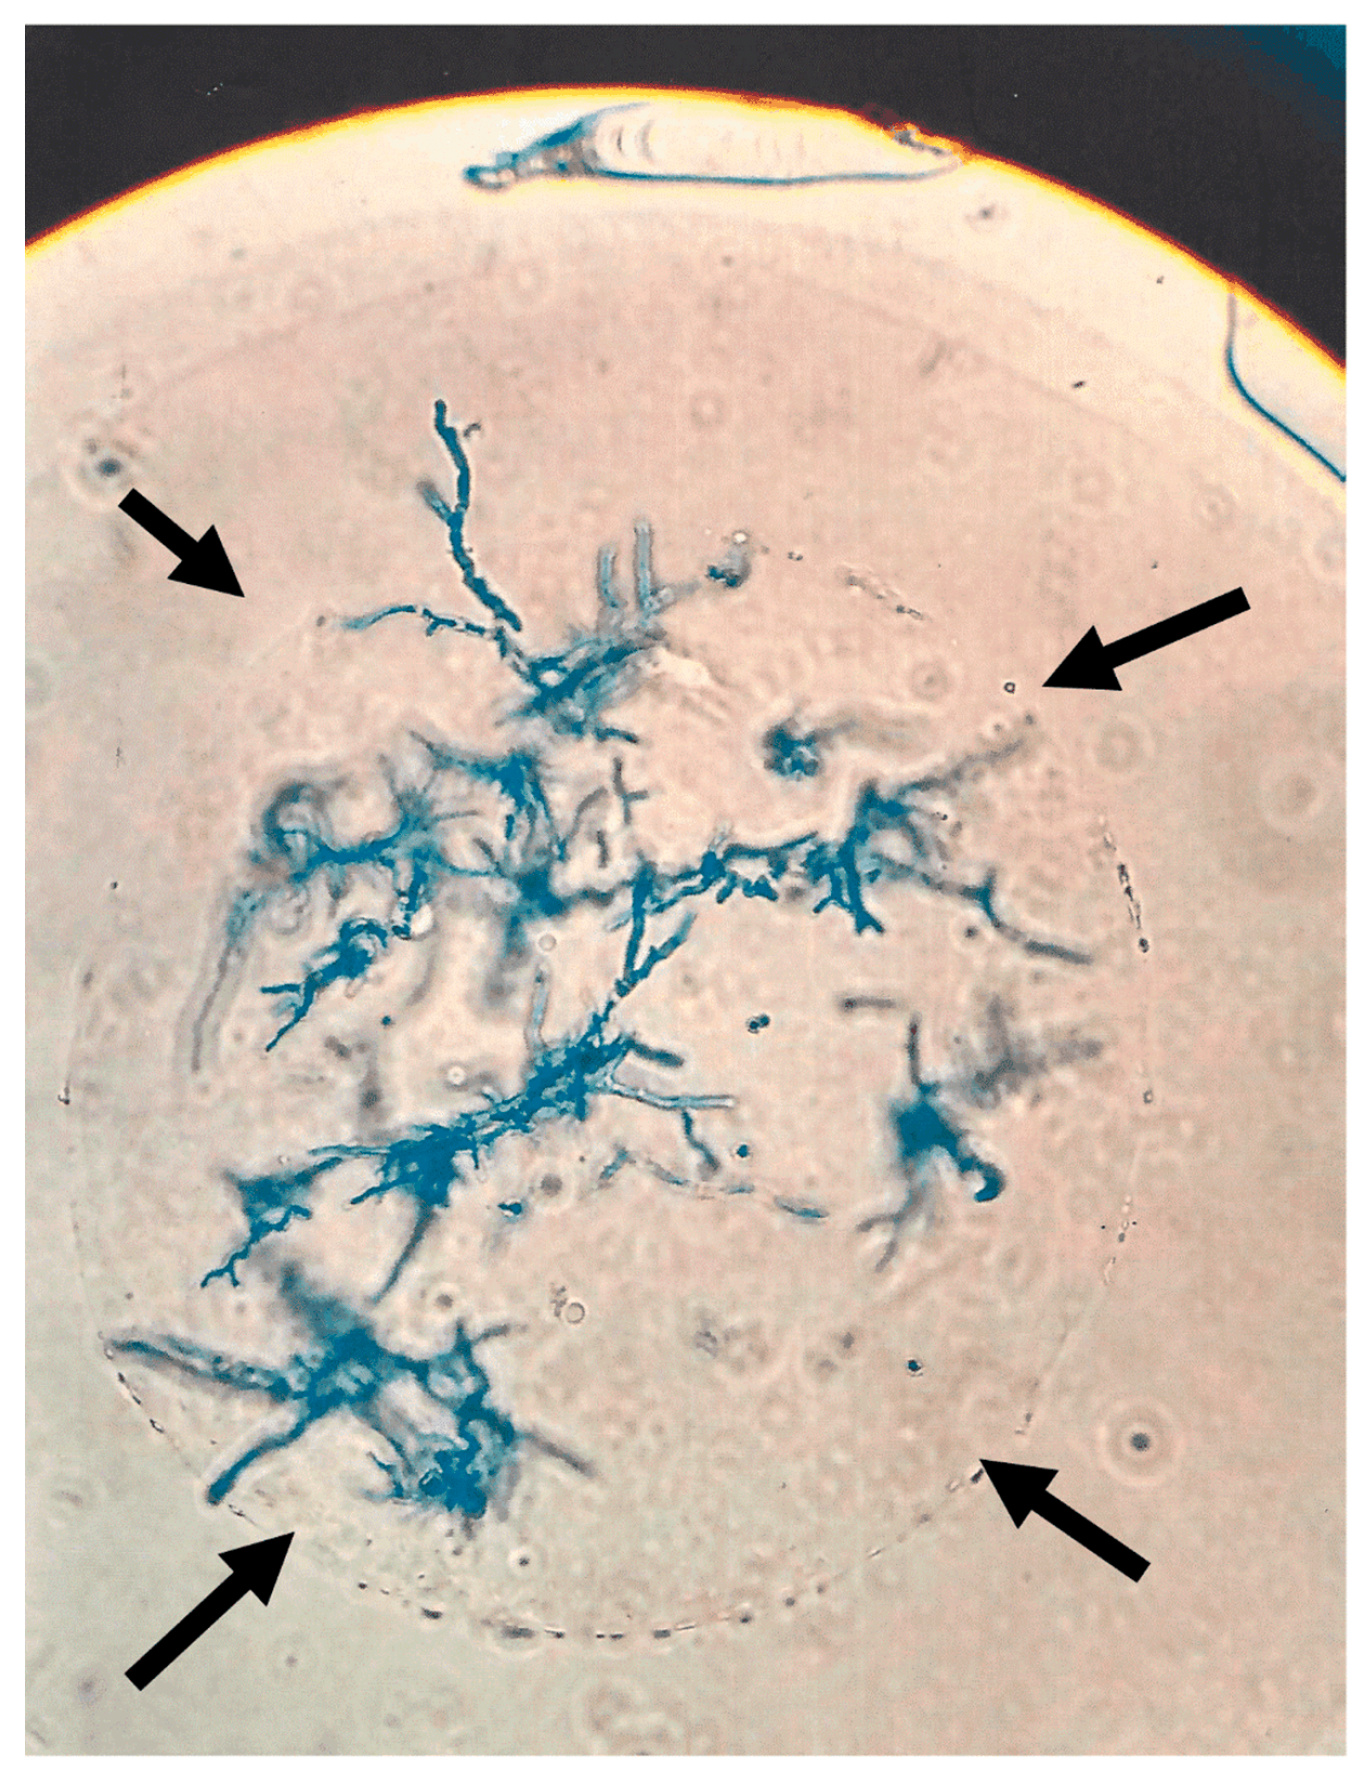

3.2. Pseudomonas Affects Aspergillus Growth in Mice When Located in Close Proximity to the Fungus

3.4. Interaction of Bead-Bound Aspergillus and Pseudomonas In Vitro